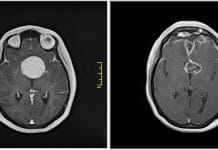

Новосибирские хирурги удалили гигантскую опухоль у пациентки из Армении

Нейрохирурги НИИТО удалили из головы пациентки из Армении огромную опухоль. Из-за нее 34-летняя Кристина Овсепян постепенно теряла зрение.

Как сообщает пресс-служба НИИТО, пропадать зрение у...